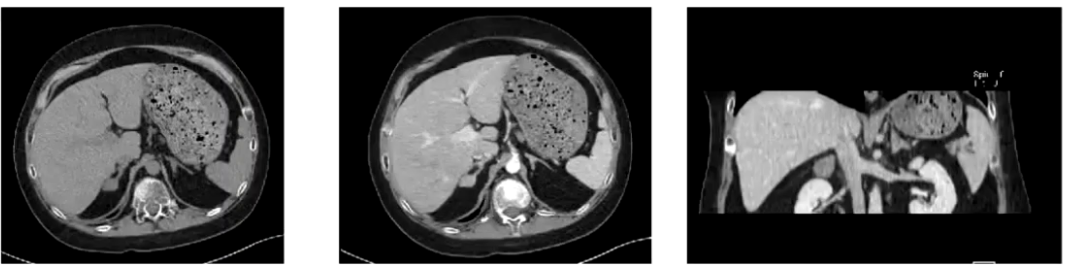

CT:肺部CT提示少量炎症;肾上腺CT平扫加增强显示右侧肾上腺椭圆形低密度影,增强后均匀强化,左侧肾上腺结合部内支不规则、强化不均匀,三维重建可见右侧团块及左侧可疑结节。